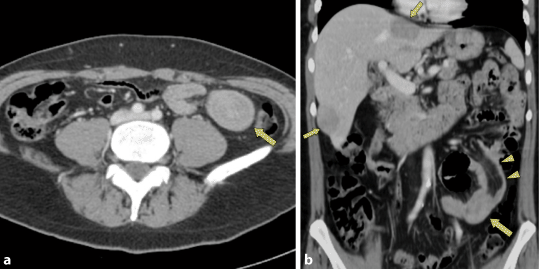

Ein 55-jähriger Patient wurde wegen Gewichtsverlusts und intermittierenden krampfartigen Bauchschmerzen auswärts zu einer Computertomographie (CT) von Thorax und Abdomen zugewiesen. Diese zeigte die Invagination eines etwa 10 cm langen Dünndarmsegments mit einer intraluminalen Raumforderung am distalen Ende (Abb. 1). Es zeigte sich keine Dilatation der vorgeschalteten Dünndarmabschnitte. Weiter fanden sich 3 hepatale, maximal 5 cm große hypovaskularisierte Tumoren und vergrößerte Lymphknoten im rechten Mittelbauch.

Abb. 1

a Die kontrastmittelverstärkte MDCT zeigt eine intraluminale Raumforderung im Dünndarm (Pfeil), welche in der koronalen multiplanaren Rekonstruktion (b) besser zu erkennen ist (Pfeil). Überdies erkennt man hier gut die Invagination des Darms mit Einstülpung von mesenterialem Fettgewebe in das Darmlumen (Pfeilspitzen). Außerdem erkennt man solide intrahepatische Tumoren (kleine Pfeile)